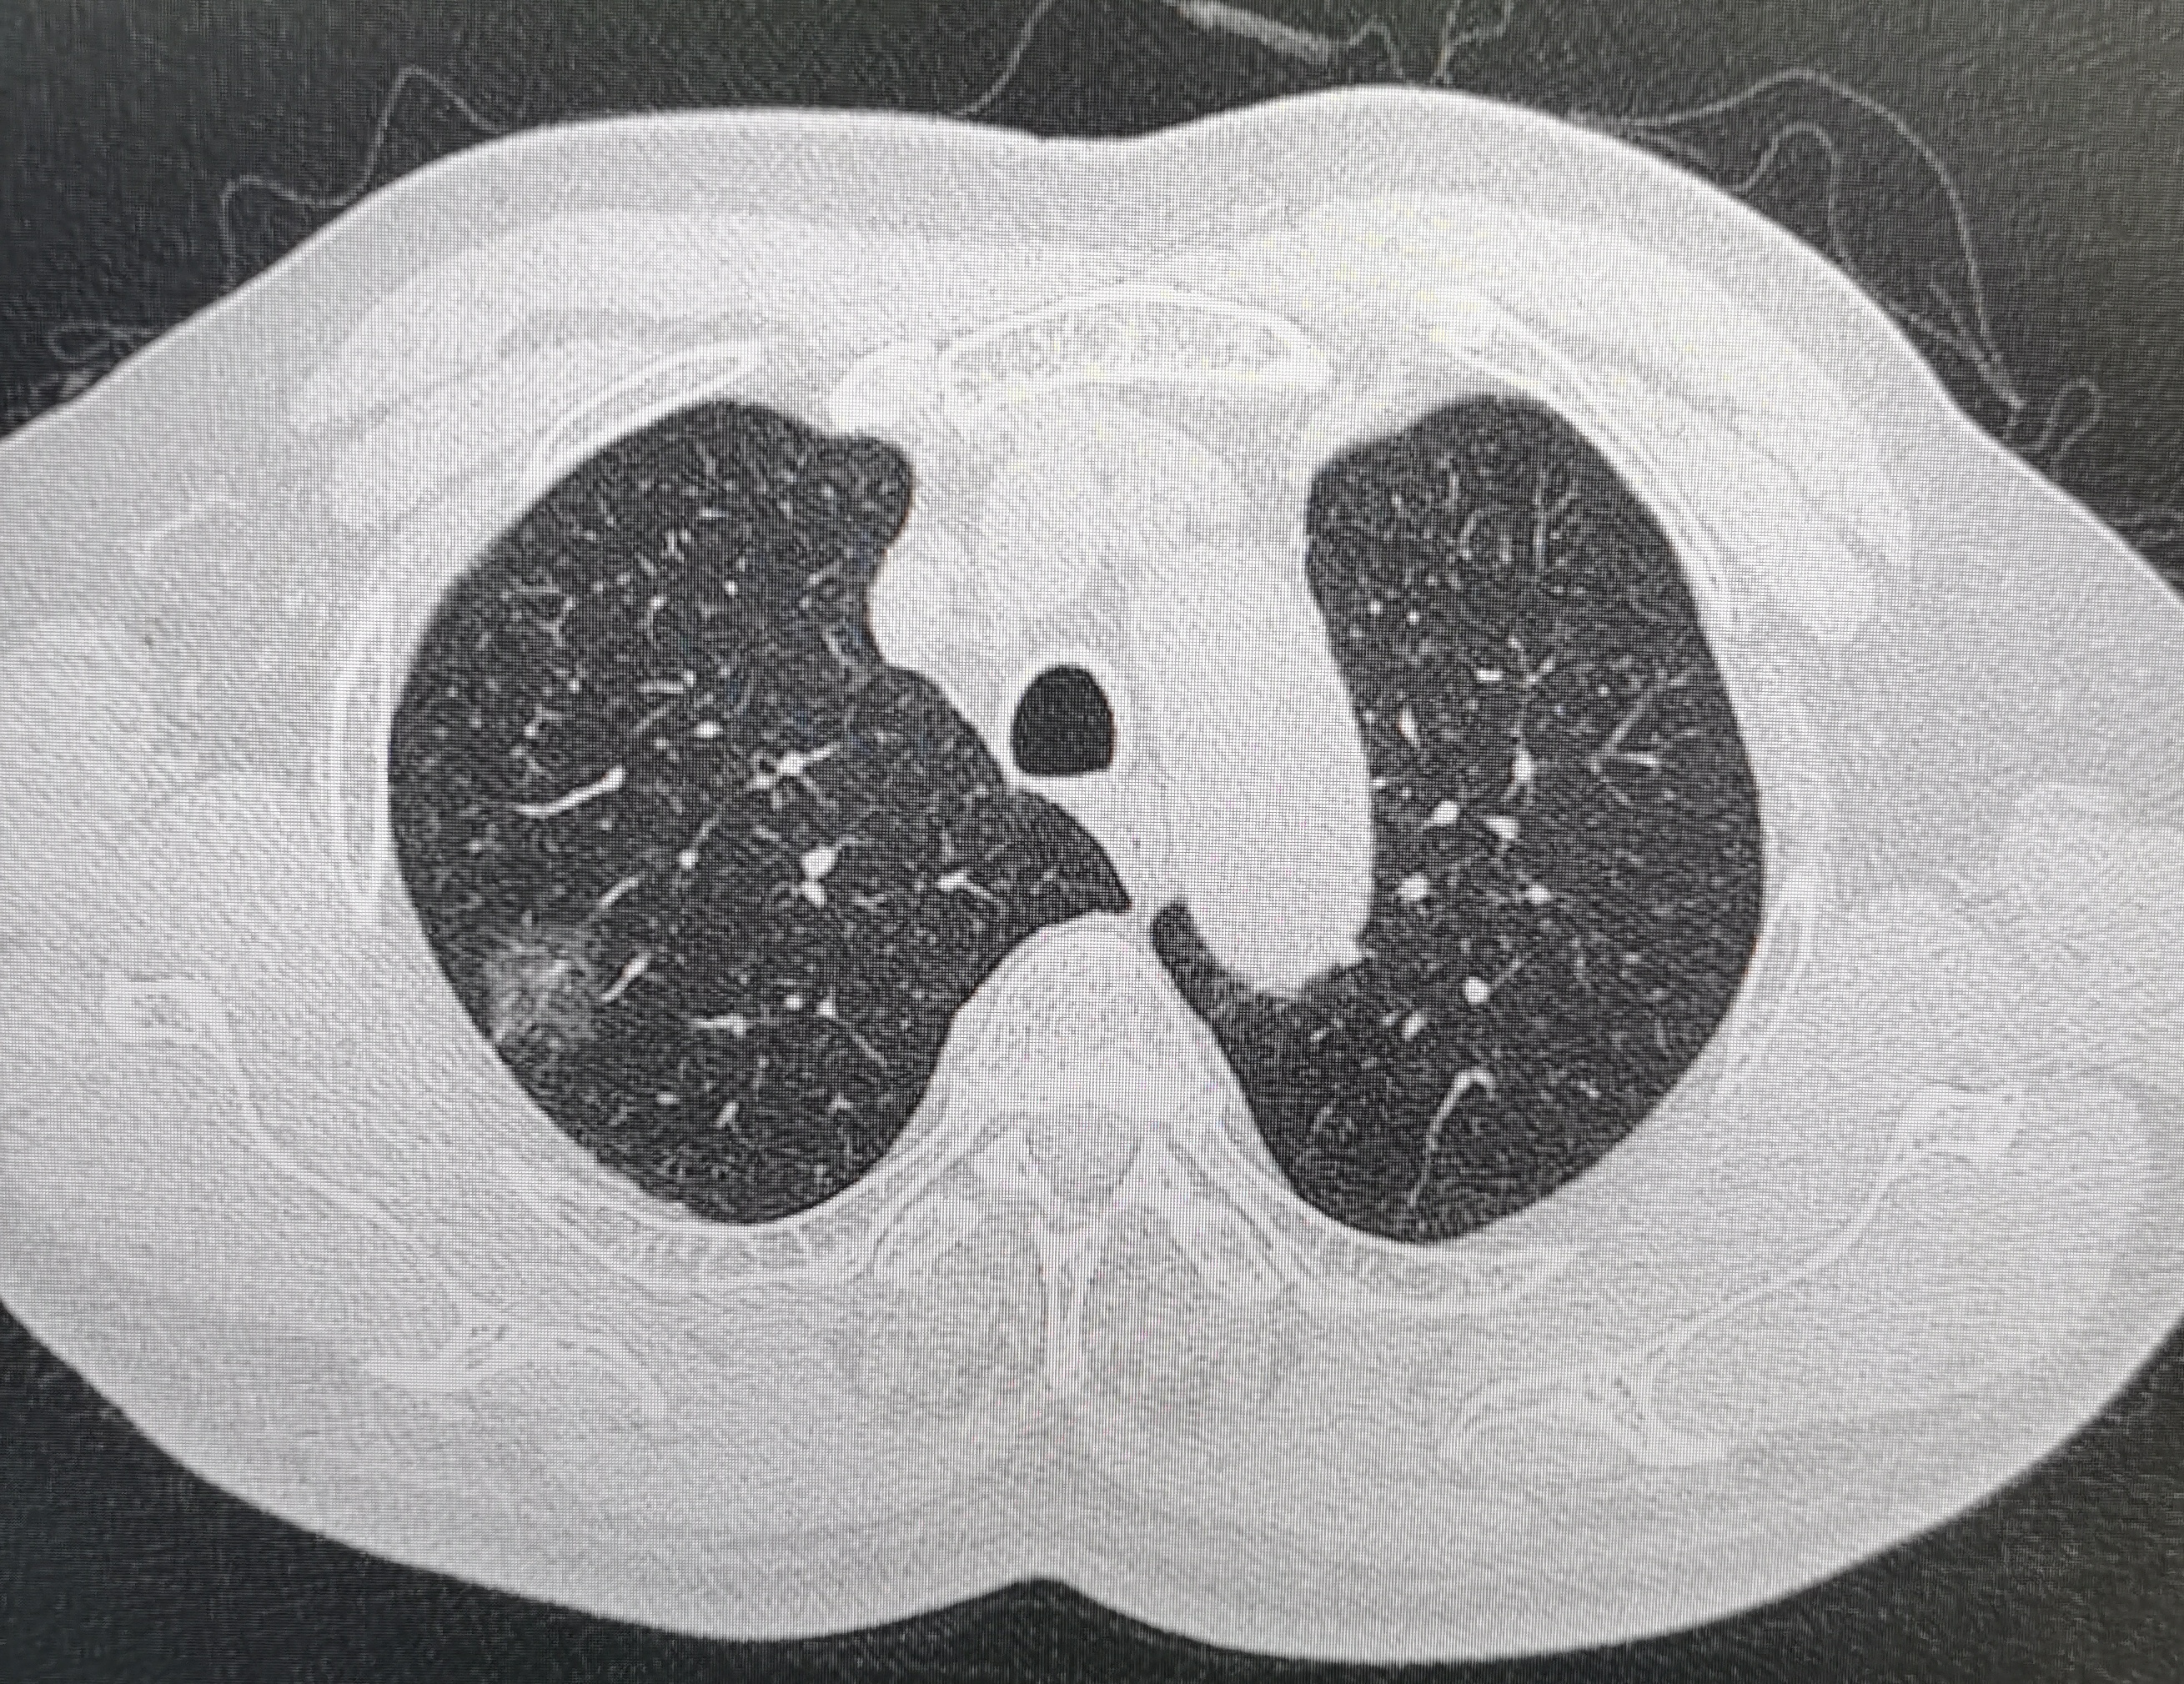

主持人:各位網(wǎng)友大家好,歡迎來到大眾網(wǎng)演播室,今年4月15日至21日是第28個(gè)全國腫瘤防治宣傳周,今年宣傳周的主題是“癌癥防治早早行動”,旨在積極倡導(dǎo)每個(gè)人做自己健康的第一責(zé)任人,正確認(rèn)識癌癥、積極防控癌癥,樹立癌癥三級預(yù)防理念。為了讓大家了解更多的腫瘤防治健康知識,提高生活質(zhì)量,近期我們相繼邀請到山東第一醫(yī)科大學(xué)第三附屬醫(yī)院的幾位相關(guān)專家,為大家講解癌癥的早期癥狀、肺結(jié)節(jié)、乳腺癌、氣管鏡在肺癌中應(yīng)用等相關(guān)知識。今天來到演播室的專家是,山東第一醫(yī)科大學(xué)第三附屬醫(yī)院胸外科副主任高玉軍。高主任您好。高玉軍:主持人你好,大家好,我是高玉軍。一、主持人:高主任,日常生活中大家都知道肺癌的發(fā)病率很高,到底高到什么程度?醫(yī)學(xué)界在降低因肺癌死亡率方面有什么措施嗎?高玉軍:由于吸煙、環(huán)境等各方面因素,目前全球肺癌的發(fā)病率和死亡率呈上升趨勢,我國肺癌發(fā)病率也是逐年增長,目前以位居腫瘤發(fā)病率第一位,已經(jīng)超越心腦血管病發(fā)病率。近十幾年女性腺癌的發(fā)病率升高明顯,僅次于乳腺癌的發(fā)病率。雖然肺癌的治療在逐年進(jìn)步,但是死亡率仍非常高,肺癌5年生存率仍徘徊在20%。所以醫(yī)學(xué)界做了大量的工作,以降低肺癌死亡率,2011年,美國的一項(xiàng)重要的全國性肺癌篩查臨床試驗(yàn)結(jié)果顯示:低劑量螺旋CT(LDCT)篩查與胸部X射線篩查相比,LDCT篩查可降低肺癌死亡率20%。這是國際上肺癌篩查臨床診斷試驗(yàn)研究最重要結(jié)果之一。所以通過胸部CT篩查,可以發(fā)現(xiàn)早期肺癌,然后及時(shí)治療,取得非常高的生存率。二、主持人:現(xiàn)在大家會發(fā)發(fā)現(xiàn)查體胸部CT報(bào)告單上出現(xiàn)肺結(jié)節(jié)的頻率非常高,能解釋什么是肺結(jié)節(jié)嗎?高玉軍:肺結(jié)節(jié)是指邊界清楚、孤立的、圓形或類圓形的直徑小于3厘米的肺部病變??梢允菒盒越Y(jié)節(jié),也可能是良性或炎性結(jié)節(jié)等。依據(jù)CT影像學(xué)表現(xiàn)分為純磨玻璃樣結(jié)節(jié);混合磨玻璃樣結(jié)節(jié);實(shí)性結(jié)節(jié)。純磨玻璃樣結(jié)節(jié)是影像學(xué)特征,指肺內(nèi)淡薄的稍高密度影,不能完全掩蓋正常的肺紋理。病理學(xué)基礎(chǔ)是肺泡壁增厚;肺泡腔塌陷。混合磨玻璃樣結(jié)節(jié)是在磨玻璃結(jié)節(jié)中伴有實(shí)性成份的影像學(xué)表現(xiàn)。三主持人:為什么磨玻璃結(jié)節(jié)被越來也多的關(guān)注高玉軍:因?yàn)榇罅康哪ゲAЫY(jié)節(jié)被查體發(fā)現(xiàn),其中部分會發(fā)展成肺癌,磨玻璃結(jié)節(jié)的惡性率高于實(shí)性節(jié),混合磨玻璃樣結(jié)節(jié)的惡性率高達(dá)63%。雖然磨玻璃結(jié)節(jié)惡變率高,但是其肺癌的發(fā)展比較慢,惡性程度低,與實(shí)性結(jié)節(jié)發(fā)展的肺癌有明顯的不同,所以大家都十分關(guān)注磨玻璃結(jié)節(jié)。目前醫(yī)學(xué)界在其影像特征、病理診斷、胸外科微創(chuàng)手術(shù)干預(yù)及預(yù)后的認(rèn)識逐漸深入,但是,其發(fā)病的機(jī)理,干預(yù)的時(shí)機(jī),干預(yù)的方式,隨訪期限等認(rèn)識需要繼續(xù)研究。四、主持人:通過體檢發(fā)現(xiàn)了肺結(jié)節(jié)應(yīng)該怎么辦呢?高玉軍:在平時(shí)工作中發(fā)現(xiàn)大部分就醫(yī)者都比較焦慮、不安甚至恐懼。有少部分就醫(yī)者不重視,認(rèn)為我沒有癥狀,能吃能睡,怎么會是肺癌呢,就不再復(fù)查,等出現(xiàn)咳嗽時(shí),到醫(yī)院一檢查,發(fā)現(xiàn)是晚期肺癌了,把能治愈的早期肺癌拖成了不能治愈的晚期肺癌。還有部分就醫(yī)者不管什么性質(zhì),就要求手術(shù)切除,一切了之。以上這些態(tài)度都是不對的,研究數(shù)據(jù)提示我國肺結(jié)節(jié)檢出率為20%-40%,惡性比率2%-3.6%。研究數(shù)據(jù)顯示78%純磨玻璃結(jié)節(jié)5年是穩(wěn)定的。所以大家要明確以下觀點(diǎn):肺結(jié)節(jié)≠肺癌;發(fā)現(xiàn)肺結(jié)節(jié)一定要到醫(yī)院找專業(yè)醫(yī)生就診,比如胸外科、影像科、呼吸科醫(yī)生來判斷結(jié)節(jié)的性質(zhì),醫(yī)生是通過結(jié)節(jié)的位置、結(jié)節(jié)的大小、結(jié)節(jié)的影像學(xué)表現(xiàn)判斷結(jié)節(jié)的危險(xiǎn)度(高危、中危、低危)。高危者需要立即住院手術(shù);中低危者選擇定期隨訪。所以一定要理性的看待肺結(jié)節(jié),選擇合理的處理策略。五主持人:怎么區(qū)分肺結(jié)節(jié)的良惡性高玉軍:第一要看患者的年齡,年輕患者的惡性率要遠(yuǎn)低于老年患者,30歲人群中結(jié)節(jié)惡性率1%-5%,70歲以上人群結(jié)節(jié)惡性率高達(dá)80%。第二影像學(xué)特征結(jié)節(jié)越大,惡性幾率越高,形態(tài)學(xué)表現(xiàn)(共有15項(xiàng)):密度(實(shí)性、亞實(shí)性)形狀(圓形或橢圓形、三角形或多邊性)邊緣(光滑、分葉、毛刺)內(nèi)部特征(脂肪、鈣化、空洞)復(fù)雜表現(xiàn)(胸膜反應(yīng)、支氣管充氣征、空泡征、囊腔、血管聚集)第三手術(shù)切除或穿刺取組織病理診斷第四比較小的純磨玻璃結(jié)節(jié),沒有明顯惡性特征的,可以定期隨訪。六、主持人:什么情況下需要隨訪,隨訪多長時(shí)間,隨訪對預(yù)后有影響嗎?高玉軍:直徑小于6mm肺結(jié)節(jié),或沒有惡性影像學(xué)特征的肺結(jié)節(jié)需要隨訪。隨訪頻率依據(jù)隨訪指南,開始為3-6個(gè)月一次,如果結(jié)節(jié)穩(wěn)定,6-12個(gè)月一次,在隨訪期間結(jié)節(jié)出現(xiàn)增大或?qū)嵭猿煞菰龆?,就要終止隨訪,考慮手術(shù)干預(yù)。依據(jù)肺結(jié)節(jié)倍增時(shí)間(實(shí)質(zhì)性肺結(jié)節(jié)的平均倍增時(shí)間為149天,純磨玻璃結(jié)節(jié)的平均倍增時(shí)間為813天,混合性磨玻璃結(jié)節(jié)的平均倍增時(shí)間為457天),隨訪頻率一般為3-6個(gè)月,在結(jié)節(jié)的倍增時(shí)間內(nèi),能及時(shí)發(fā)現(xiàn)增長結(jié)節(jié)。對于實(shí)質(zhì)性肺結(jié)節(jié),若隨訪時(shí)間超過2年未見生長,通??紤]良性可能大。但是對于磨玻璃密度結(jié)節(jié),因其倍增時(shí)間長,故隨訪時(shí)間應(yīng)3-5年。由于隨訪的多是癌前病變或是惰性癌,結(jié)節(jié)增大后再手術(shù),對生存沒有影響。七、主持人:高危肺結(jié)節(jié)的怎么處理?高玉軍:不推薦隨訪或等待。需要術(shù)前明確病理診斷者,可以選擇經(jīng)皮穿刺活檢或磁導(dǎo)航支氣管鏡等檢查。推薦胸腔鏡微創(chuàng)手術(shù)。立體定向放療治療(SBRT):不能耐受手術(shù)或不愿手術(shù)者。微波消融、射頻消融:不適合手術(shù)和放療者。八主持人:發(fā)現(xiàn)磨玻璃結(jié)節(jié)術(shù)前需要行PET/CT檢查或穿刺活檢嗎?高玉軍:由于磨玻璃結(jié)節(jié)的實(shí)性成份很少,突變的細(xì)胞代謝低,增值慢,所PET/CT檢查陽性率非常低。由于實(shí)性成份少,穿刺活檢取的病變組織也會很少,病理診斷陽性率也非常低,所以術(shù)前不建議做。九、主持人:胸腔鏡微創(chuàng)手術(shù)的方式,優(yōu)勢是那些?高玉軍:胸腔鏡技術(shù)的發(fā)展是胸部外科技術(shù)的巨大進(jìn)步,使胸部外科進(jìn)入微創(chuàng)手術(shù)時(shí)代,傳統(tǒng)開胸手術(shù)的切口長15-20厘米,切斷各層肌肉,還需要把肋骨撐開。現(xiàn)在只需在胸腔切1-2個(gè)2-3厘米的小口,完全在胸腔鏡下完成各種手術(shù)操作,解剖更精細(xì),層次更清楚,術(shù)中創(chuàng)傷更少,對機(jī)體的內(nèi)環(huán)境破壞較輕,創(chuàng)傷應(yīng)激反應(yīng)更輕。術(shù)后并發(fā)癥少,肺功能損失少,術(shù)后恢復(fù)快。對于小于2cm的結(jié)節(jié),以毛玻璃成份占主,病理是原位癌、微浸潤腺癌等早期病變,可以選擇創(chuàng)傷更小的肺段、楔形切除。早期肺癌術(shù)后5年生產(chǎn)率80%-90%,原位癌和微浸潤腺癌5年生產(chǎn)率100%。十主持人:我們醫(yī)院胸外科開展了那些工作。高玉軍:已開展肺癌、食管癌、賁門癌、縱膈腫瘤等各類手術(shù)500余臺,在肺癌的外科治療及綜合治療上積累了豐富的經(jīng)驗(yàn)。完善肺癌TNM分期,規(guī)范化開展中晚期肺癌術(shù)前新輔助治療、術(shù)后化療、靶向藥物、免疫藥物輔助治療。Ⅲ期肺癌嚴(yán)格按照院內(nèi)多學(xué)科討論方案治療,發(fā)揮外科手術(shù)優(yōu)勢,爭取患者獲益最大化。在研究診治早期肺癌,特別是肺磨玻璃結(jié)節(jié)(GGO)的診斷與治療取得了一定的成績,已成功治療多例肺單發(fā)和多發(fā)磨玻璃結(jié)節(jié)樣癌,取得良好的效果。常規(guī)開展胸腔鏡下肺葉、肺段級食管癌的微創(chuàng)手術(shù),減少了患者肺功能損失,減輕了術(shù)后疼痛,減少了住院時(shí)間,降低了住院費(fèi)用。通過以上努力,我科胸部腫瘤患者手術(shù)并發(fā)癥非常低,患者術(shù)后生存率非常高。十一主持人:胸部手術(shù)之后有哪些注意問題高玉軍:術(shù)后要定期隨訪,術(shù)后2年內(nèi)6個(gè)月隨訪一次,3-5年每年隨訪一次,5年后每年隨訪一次。規(guī)律作息,合理飲食,適度的鍛煉,特別是呼吸鍛煉。避免接觸刺激性氣體、盡量保持舒適生活環(huán)境,避免肺部感染等。主持人:謝謝高主任的耐心講解,如果大家有疑問或者想就診可以到山東第一醫(yī)科大學(xué)第三附屬醫(yī)院胸外科高主任的門診進(jìn)行就醫(yī),地址是山東第一醫(yī)科大學(xué)第三附屬醫(yī)院門診樓二樓外科3診室每周四全天,電話13655315759高玉軍山東第一醫(yī)科大學(xué)第三附屬醫(yī)院胸外科副主任醫(yī)師科室副主任1365531575

廣大患者很擔(dān)心肺磨玻璃結(jié)節(jié)手術(shù)后的預(yù)后,是否會術(shù)后復(fù)發(fā)轉(zhuǎn)移,從胸外科專業(yè)角度和大家解讀,總結(jié)一下結(jié)節(jié)術(shù)后預(yù)后情況:1.術(shù)后不會復(fù)發(fā)的人群:原位癌2.術(shù)后未見復(fù)發(fā)病例的人群:微浸潤腺癌3.術(shù)后極少復(fù)發(fā)的人群:純磨玻璃樣的浸潤性腺癌,縱膈窗不可見的混雜磨玻璃結(jié)節(jié),和CTR<0.25混雜磨玻璃結(jié)節(jié)4.術(shù)后很少復(fù)發(fā)的人群:CTR<0.5的混雜磨玻璃結(jié)節(jié)5.術(shù)后小概率復(fù)發(fā)(5%-12%):CTR>0.5的人群